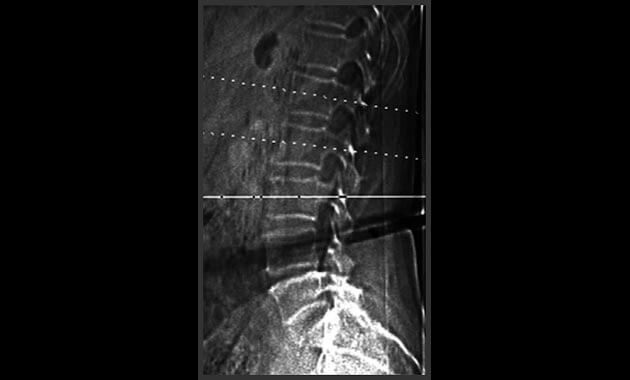

Pioneered at UCSF, quantitative computed tomography (QCT) is a test to measure bone mineral density (BMD). It is performed using a computed tomography (CT) scanner and results in a 3D image. Hip and lumbar spine are the most common choices for evaluation with QCT.